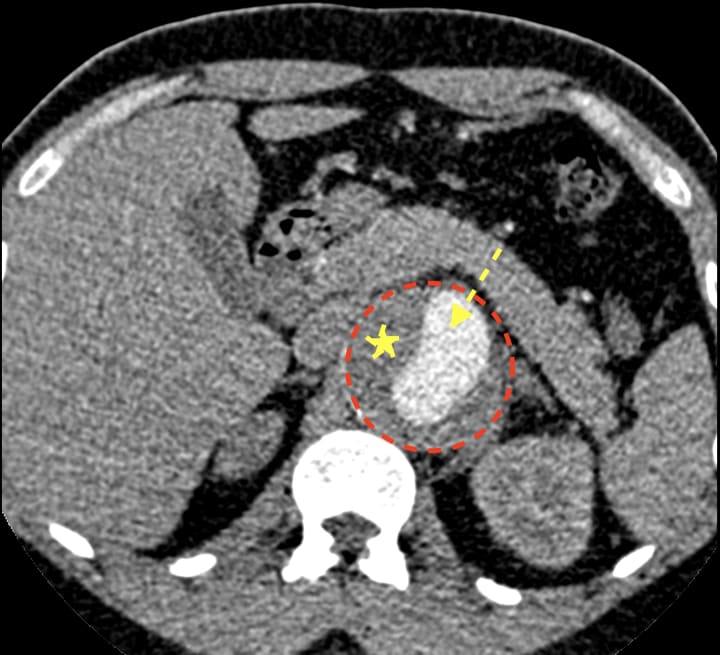

An aortic aneurysm arises when the walls of the aorta—the primary vessel transporting blood from the heart—swell or expand. Although aneurysms can develop anywhere along the aorta, the abdomen is the most frequent location.

The majority of AAAs are small when detected through screening processes or via radiological exams (e.g., ultrasound, computed tomography, magnetic resonance) performed for unrelated reasons. While small AAAs typically do not necessitate treatment, regular monitoring is advised to track the aneurysm's size and any associated symptoms.

The risk of rupture for small aneurysms (under 4.0 centimeters) is considerably lower than that of large aneurysms (over 6.0 centimeters). Besides size, the rate of AAA rupture is also influenced by the aneurysm's expansion rate. Evidence indicates that aneurysms grow at an average pace of 0.3 to 0.4 centimeters per year (1 inch = 2.5 cm), with larger aneurysms expanding more quickly than smaller ones.